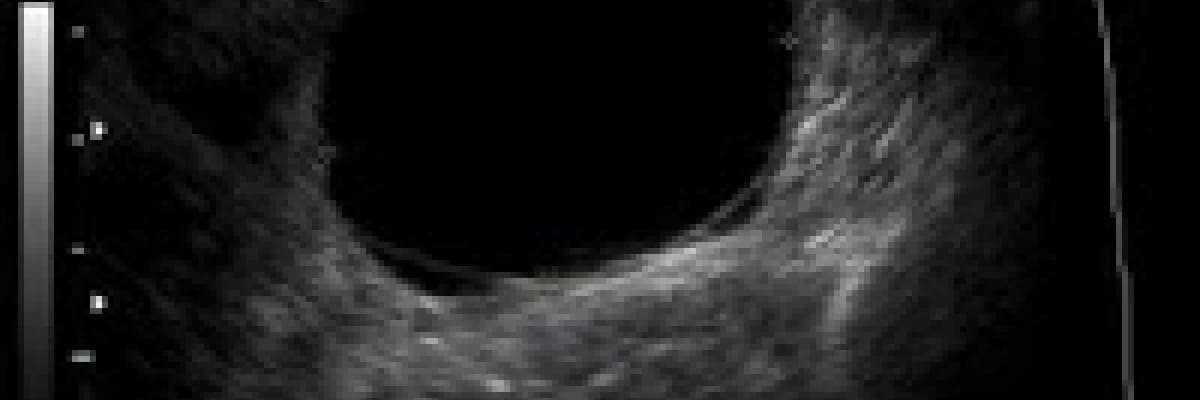

Laparoskopik (kapalı ameliyat) yöntemle over kisti ameliyatının dezavantajı kistin malign (kötü huylu) olması durumunda karın içerisine malign hücrelerin dağılması riskidir, bu prognozu kötü etkiler. Bu nedenle malignite riski olan durumlarda laparoskopik yöntem tercih edilmez. Uniloküler ince cidarlı kistler postmenopozal hastada bile çok yüksek oranda benign olmaktadırlar, bu nedenle bu tür kistlerde mümkünse laparoskopi tercih edilir. Kistte papiller formasyon, 2 mm’den kalın septum veya solid alan görüntüleri varsa malignite riski artar bu durumda laparoskopi tercih edilmez (kaynak). Hastada asit olması, peritoneal kitle veya büyük lenf nodları olması malignite lehine diğer bulgulardır. Özetle hastada malignite şüphesi veya laparoskopi açısından diğer kontrendikasyonlar yoksa over kistinin tedavisi için (kistektomi veya ooforektomi) öncelikle laparoskopik yöntem tercih edilir.